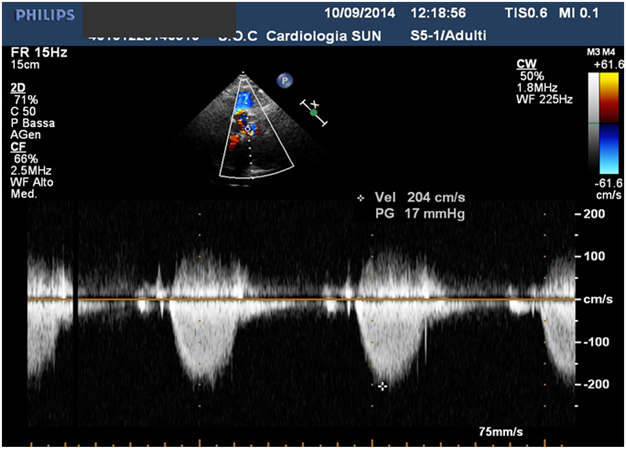

Residual mild VSD.

No residual RVOT obstruction.

Echocardiography

- Residual mild VSD.

- No residual right outflow tract obstruction.

- Good biventricular size and function.

- Slight biatrial dilatation.